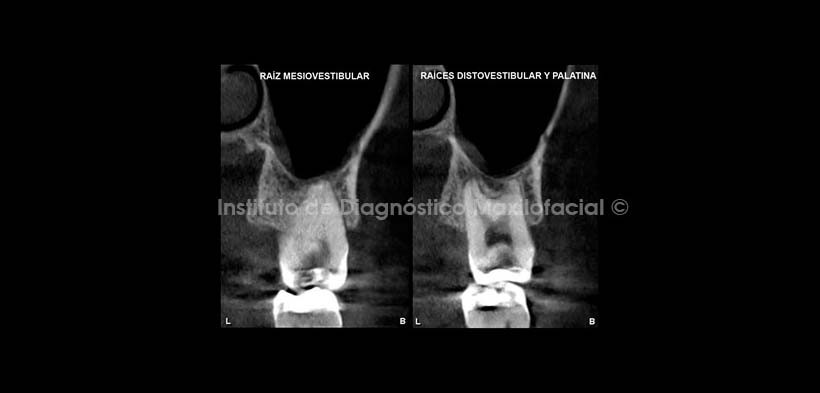

En cortes axiales de pieza 2.6 a diferentes niveles (Fig. 3) se observa en el tercio cervical la obturación de cuatro conductos radiculares (doble conducto en la raíz mesiovestibular). En el tercio medio se observa el compromiso a nivel de la furcación; y en el tercio apical se evidencia el proceso osteolítico condicionado por la sobreobturacion de conductos, asi como la erosion de la tabla ósea vestibular a nivel apical de raíz mesiovestibular.

En cortes transaxiales de la pieza 2.6 (Fig. 4), se muestra la amplia zona de rarefaccion y la erosión del piso del seno maxilar en relacion con la raiz palatina, así mismo se observa una imagen hipodensa a nivel del tercio medio de esta, probablemente correspondiente a un proceso de reabsorcion radicular interna. Además se evidencia la deficiente obturación de los conductos radiculares. En la Pieza 2.7 (Fig. 5) se observa la restauración coronaria junto a una lesion cariosa recidivante amplia y profunda con aparente compromiso pulpar. Nótese el acortamiento de la longitud radicular, la ausencia de constriccion cervical y la ampliación de la camara pulpar en sentido ocluso-apical, Signos tomograficos correspondientes a anomalía de la morfologia dentaria sugerente de Taurodontismo.